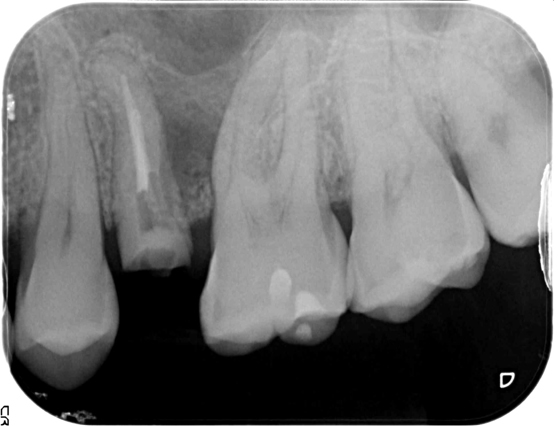

大きな穿孔(パーフォレーション)を認めるが、封鎖がきちんと行えれば根管治療にて保存可能とご提案

穿孔部をバイオセラミックにて封鎖し根管治療。経過観察1年で良好な経過と治癒傾向を確認